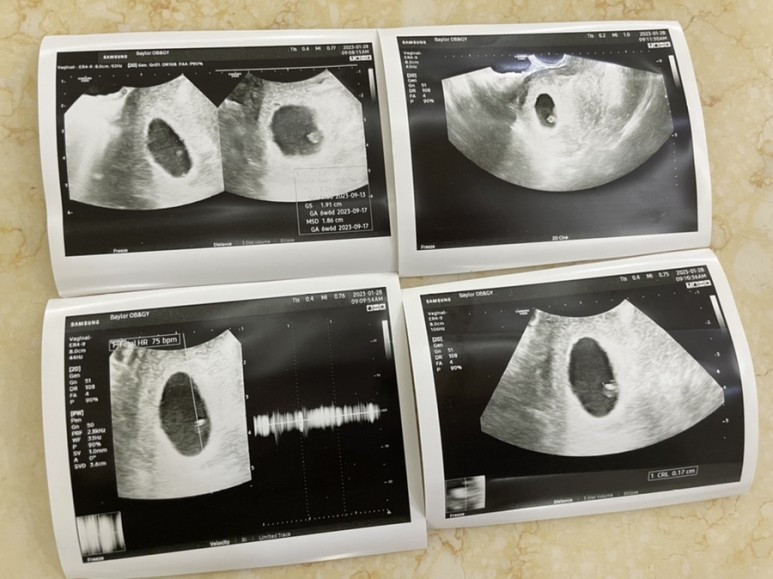

IMG_0695.jpg 잘 보인다고 하시는데 도무지 뭐가 잘 보인다는건지 이해하지 못했던 첫 초음파

동네 산부인과 가서 검사를 해보니 임신 맞다고, 애기집도 보이고 뭐 어쩌구저쩌구... 6주차라고 했던 것 같다. 당장 장거리 출장이 예정되어 있고 여러모로 마음이 싱숭생숭했다.

그래서 목요일 오후 2시 반인가 인천공항에 떨어지자 마자 캐리어 끌고 산부인과로 달려갔다ㅎㅎ 심지어 여행자보험이 아직 적용되어 있어서 건강보험 적용이 안된다고 해서 비급여로 검진을 받았다ㅎㅎ (그래도 10만원은 넘을거라 생각했는데 5~6만원 선이었던 것 같다.)

초음파로 확인하니 애기 건강히 잘 있다고, 심장소리도 더 또렷해졌다는 결과를 받았다. 유퀴즈에 나왔던 전종관 교수님께서 얘기하신 대로 정말 그냥 애기마다의 팔자인가보다. (팔자라는 표현을 쓰진 않으셨지만 내가 이해한 방식입니당)